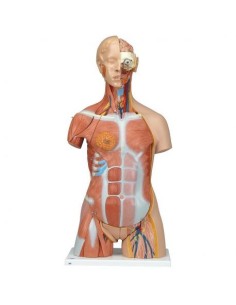

Scopri il Mondo dell’Anatomia con Modelli anatomici di Precisione

Benvenuto su Tuttoanatomia.it, il portale di riferimento in Italia per l’acquisto di modelli anatomici, poster, lettini portatili, simulatori medici e letteratura specialistica. Con i nostri modelli anatomici di 3B Scientific ed Erler Zimmer, leader mondiali nel settore, offriamo un’esperienza di apprendimento senza pari.

Modelli Anatomici Dettagliati per Ogni Necessità

Dal cranio in 22 parti con incastri magnetici ai modelli di colonna vertebrale, da quelli di articolazioni a quelli di cuore, ogni pezzo della nostra collezione è progettato per un’immersione totale nello studio dell’anatomia umana. I nostri modelli, realizzati tramite scansioni di ossa vere, garantiscono un’esperienza tattile autentica e una fedeltà di peso quasi identica agli originali.

Strumenti Didattici Innovativi per l’Educazione e la Pratica Medica

Essenziali per studenti e professionisti, i nostri modelli anatomici sono strumenti didattici che permettono di osservare le strutture anatomiche con precisione, eliminando la necessità di dissezioni o studi invasivi. Sono inoltre utili per spiegare ai pazienti le patologie, rendendo la comunicazione più efficace e risparmiando tempo prezioso.